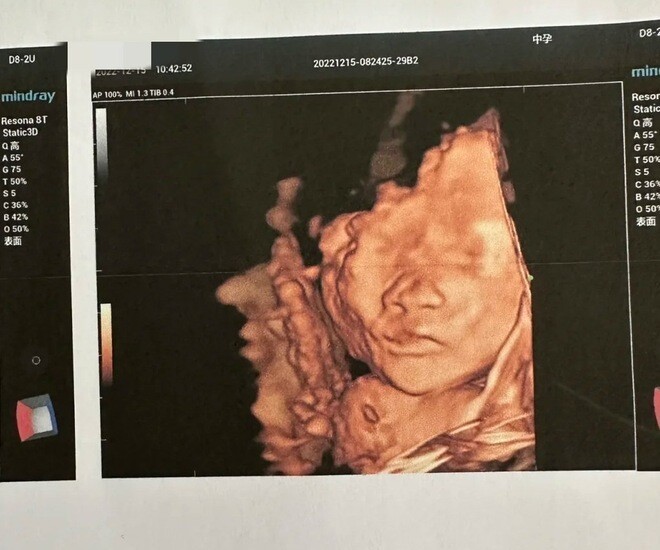

Đến ngày siêu âm ở tuần thứ 22, họ lựa chọn một bệnh viện cho phép người cha vào phòng siêu âm. Bác sĩ thoa gel lên bụng Huihui và di chuyển đầu dò. Thai nhi khá “hợp tác”, lần lượt hiện lên trên màn hình từ đôi bàn chân nhỏ, phần mông, lưng, sau đó là phía sau đầu và cuối cùng là khuôn mặt.

Đúng lúc đó, đứa trẻ đột nhiên cười toe toét.

Người chồng càng vui mừng "Nhìn kìa, em bé thực sự đang cười. Có vẻ như thai giáo trước khi sinh rất tốt đó. Đứa bé biết tôi là bố của nó".

Tuy nhiên, trái với sự hân hoan của hai vợ chồng, bác sĩ siêu âm – một người đã có nhiều năm kinh nghiệm – lại trầm giọng nhận xét rằng hình ảnh thai nhi cười không hẳn là dấu hiệu tích cực. Bác sĩ hỏi liệu thai kỳ này có được chuẩn bị kỹ lưỡng và người mẹ có bổ sung axit folic đầy đủ trong giai đoạn đầu hay không.

Sau khi xem xét kỹ hình ảnh siêu âm, bác sĩ cho biết thai nhi có dấu hiệu sứt môi – tình trạng môi trên không khép kín, khiến khi cười trông như đang “nở nụ cười bất thường”.

Bác sĩ giải thích rằng sứt môi là dị tật bẩm sinh do nhiều yếu tố gây ra, trong đó thiếu axit folic trong thai kỳ là một nguyên nhân quan trọng. Với y học hiện đại, các trường hợp nhẹ có thể phẫu thuật chỉnh hình, nhưng những ca nặng có thể ảnh hưởng đến việc ăn uống, phát âm và cả tâm lý của trẻ khi lớn lên.

Ảnh minh họa